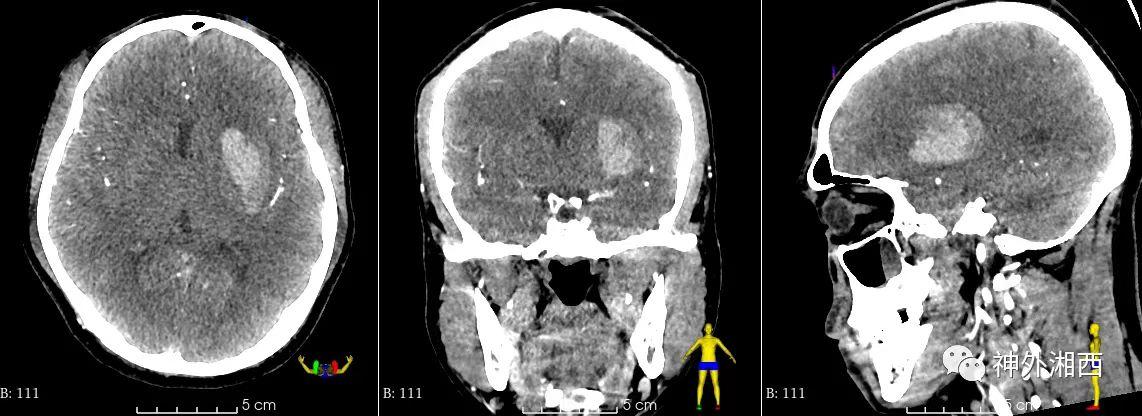

3DSlicer精准计算血肿体积:27.83ml